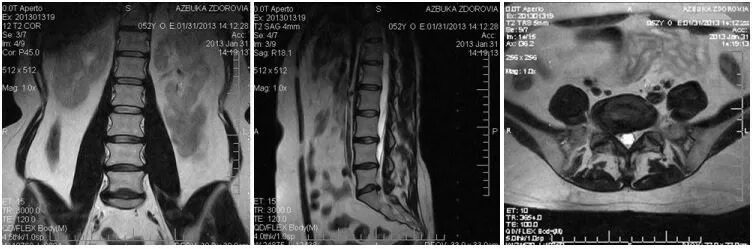

Мрт крестово поясничного отдела